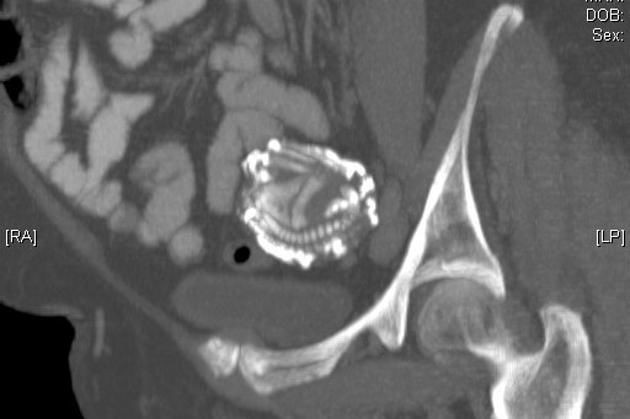

Thời gian cứ thế trôi đi, Zahra đã lên chức bà. Nhưng 46 năm sau, khi Zahra 75 tuổi, triệu chứng đau bụng lại xuất hiện. Cậu con trai nuôi đưa bà đến gặp giáo sư Taibi Ouazzani. Ông nghi ngờ có khối u buồng trứng vì bụng bà phình ra. Giáo sư Taibi tiến hành siêu âm và nhận thấy một "vật thể lạ khá lớn" không xác định được. Ông giới thiệu Zahra đến gặp một chuyên gia chụp X quang. Cuối cùng, kết quả chụp MRI xác nhận rằng nó thực sự là đứa con chưa chào đời của bà.

Bà Zahra đã mang thai ngoài tử cung, khi bào thai ngày càng to dần, nó làm vỡ ống dẫn trứng, tiếp tục phát triển trong ổ bụng và sống sót bằng cách gắn nhau của nó vào các cơ quan nội tạng trong bụng bà Zahra.

Khi các bác sĩ thực hiện phẫu thuật, họ phát hiện ra bào thai đã bị vôi hóa, là một khối cục rất rắn và đặc. Về cơ bản đó là một "em bé đá", đã gắn chặt với thành bụng và các bộ phận quan trọng trong người bà Zahra. Sau 4 tiếng phẫu thuật, các bác sĩ đã lấy ra bào thai thành công. Em bé nặng 3,2kg và dài 42cm.